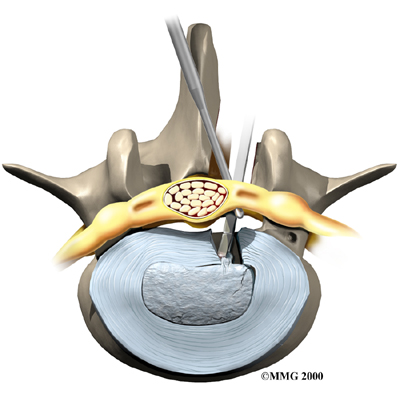

Microdiscectomy

Microdiscectomy is becoming the standard surgery for lumbar disc herniation. The procedure is used when a herniated disc is putting pressure on a nerve root. It involves carefully taking out part of the problem disc (discectomy). By performing the operation with a surgical microscope, the surgeon only needs to make a very small incision in the low back. Categorized as minimally invasive surgery, this surgery is thought to be less taxing on patients. Advocates also believe that this type of surgery is easier to perform, that it prevents scarring around the nerves and joints, and that it helps patients recover more quickly.

Related Document: FYZICAL North Richland Hills Guide to Lumbar Discectomy